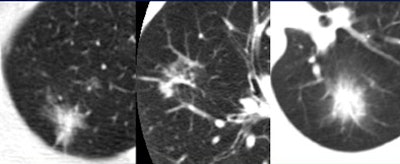

| Among 233 cancers detected in the first 1,000 patients of the ELCAP study, Henschke et al found markedly higher rates of malignancy in mixed-composition part-solid nodules. AJR, May 2002, Vol. 178:5, pp. 1053-1057. |

| Part-solid nodules with a ground-glass component have the highest rate of malignancy, according to several studies. |